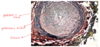

Complétez. Lors de l'hypertrophie de la média des artères pulmonaires du chat, il y a __ de la dimension des artères due à une __ et une __ provoquant une __ de la lumière. L'éthiologie est incertaine, mais __ peut causer des lésions similaires.

Lors de l'hypertrophie de la média des artères pulmonaires du chat, il y a **augmentation** de la dimension des artères due à une **hypertrophie** et une **hyperplasie** provoquant une **diminution** de la lumière. L'éthiologie est incertaine, mais **Aelurostrongylus abstrusus** peut causer des lésions similaires.